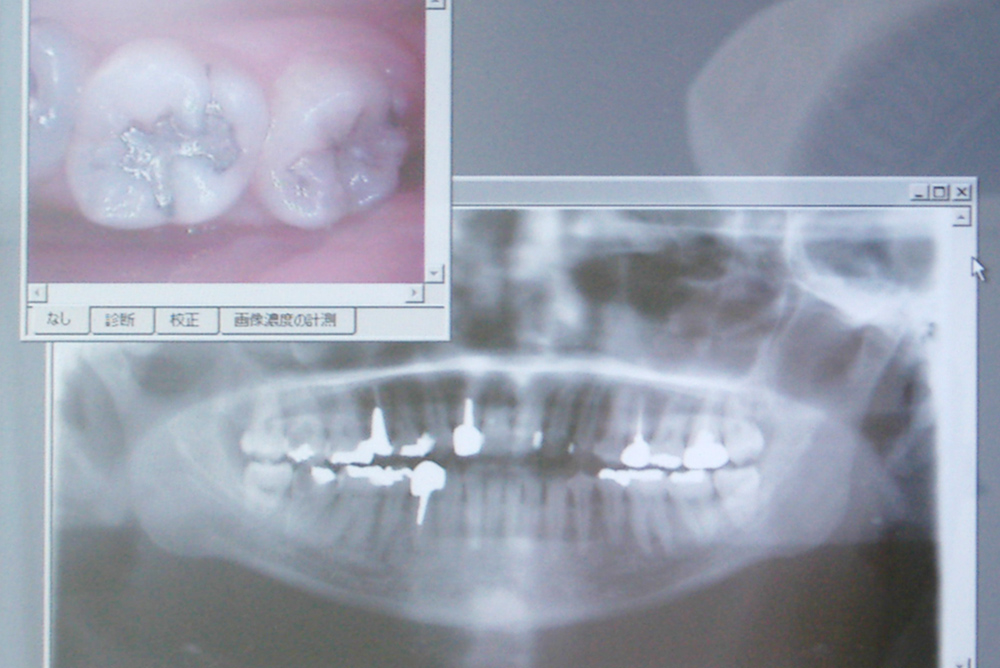

診療台に座ったまま、CCDカメラ(口腔内カメラ)により撮影した写真を確認することも可能です。

鏡でご自分の口内を確認するより、はっきりと悪い部分・良い部分をご覧になることができます。

同じモニタを使用して、レントゲン写真を見ることも可能です。

レントゲン

(デジタルX線写真)

当院では

「一部の歯を撮るレントゲン写真」

「お口全体を撮るレントゲン写真」

共にデジタル式を使用しており、従来のレントゲン機械よりも大幅に放射線量が少ないため、お体への負担も軽減します。

また、現像の手間が不必要なため、迅速に写真を確認することが可能です。 部分的に拡大して映し出すこともできますので、虫歯等の発見・確認が非常に容易となります。